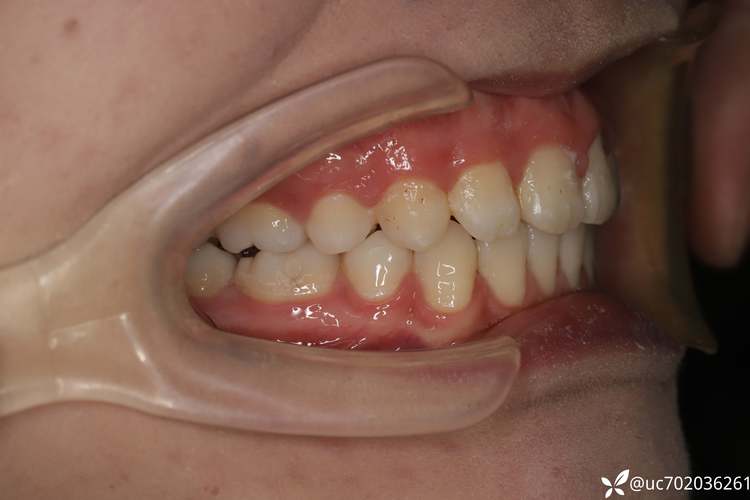

牙齿表现

牙齿异常是二类二分类的核心特征:上颌前牙(尤其是切牙)常呈唇倾状态,牙轴角度增大(U1-NA距增大,U1-NA角减小),导致深覆盖(覆盖>3mm);下颌前牙可能直立或舌倾,与上颌前牙无接触;磨牙关系完全远中,上颌第一磨牙的近中舌尖可能咬合于下颌第一磨牙的中央窝远中;部分患者伴发牙列拥挤或牙弓狭窄。